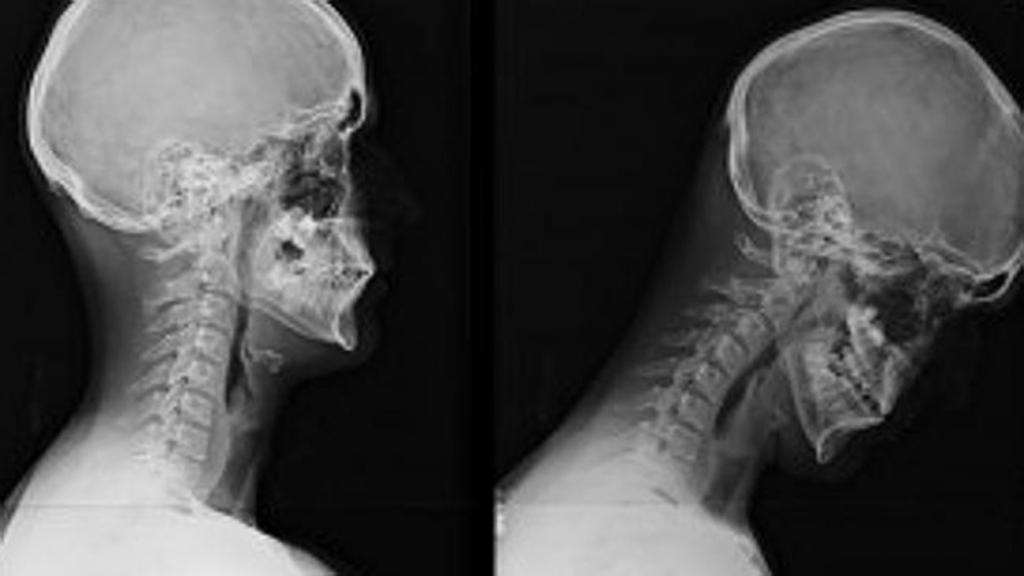

- Рентгенография — метод, оценивающий внутренние структуры организма.

Самостоятельно поставить диагноз невозможно. Чтобы убедиться в том, что сильно болит голова и шея сзади именно по причине невралгии затылочного нерва — надо пройти ряд исследований. Чаще всего необходима консультация невропатолога, расшифровка результатов КТ и МРТ, иногда может потребоваться рентгенография.

Если болит шея сзади у основания головы — следует обратиться за консультацией к неврологу. Самостоятельно выяснить причины дискомфорта невозможно. Для диагностики шейного спондилеза назначают:

- КТ (компьютерная томография) позвоночника, при помощи которой можно детально рассмотреть все плотные структуры шеи.

- МРТ позвоночника для оценки состояния мягких тканей.

- рентген шейного отдела позвоночника позволит рассмотреть степень искривления и патологии позвонков;